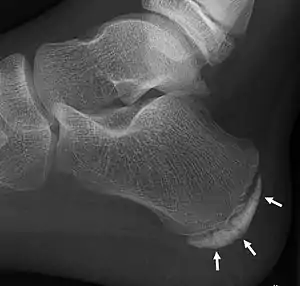

| X-ray of the foot of an 11-year-old child,showing sclerosis and fragmentation of the calcaneal apophysis. This is a sign of low sensitivity and specificity of Sever's disease, because those with Sever's disease may not have it, and it is commonly present in feet without any symptoms.[1] | |